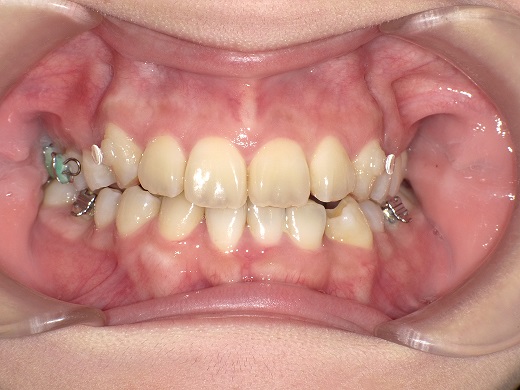

治療前正面